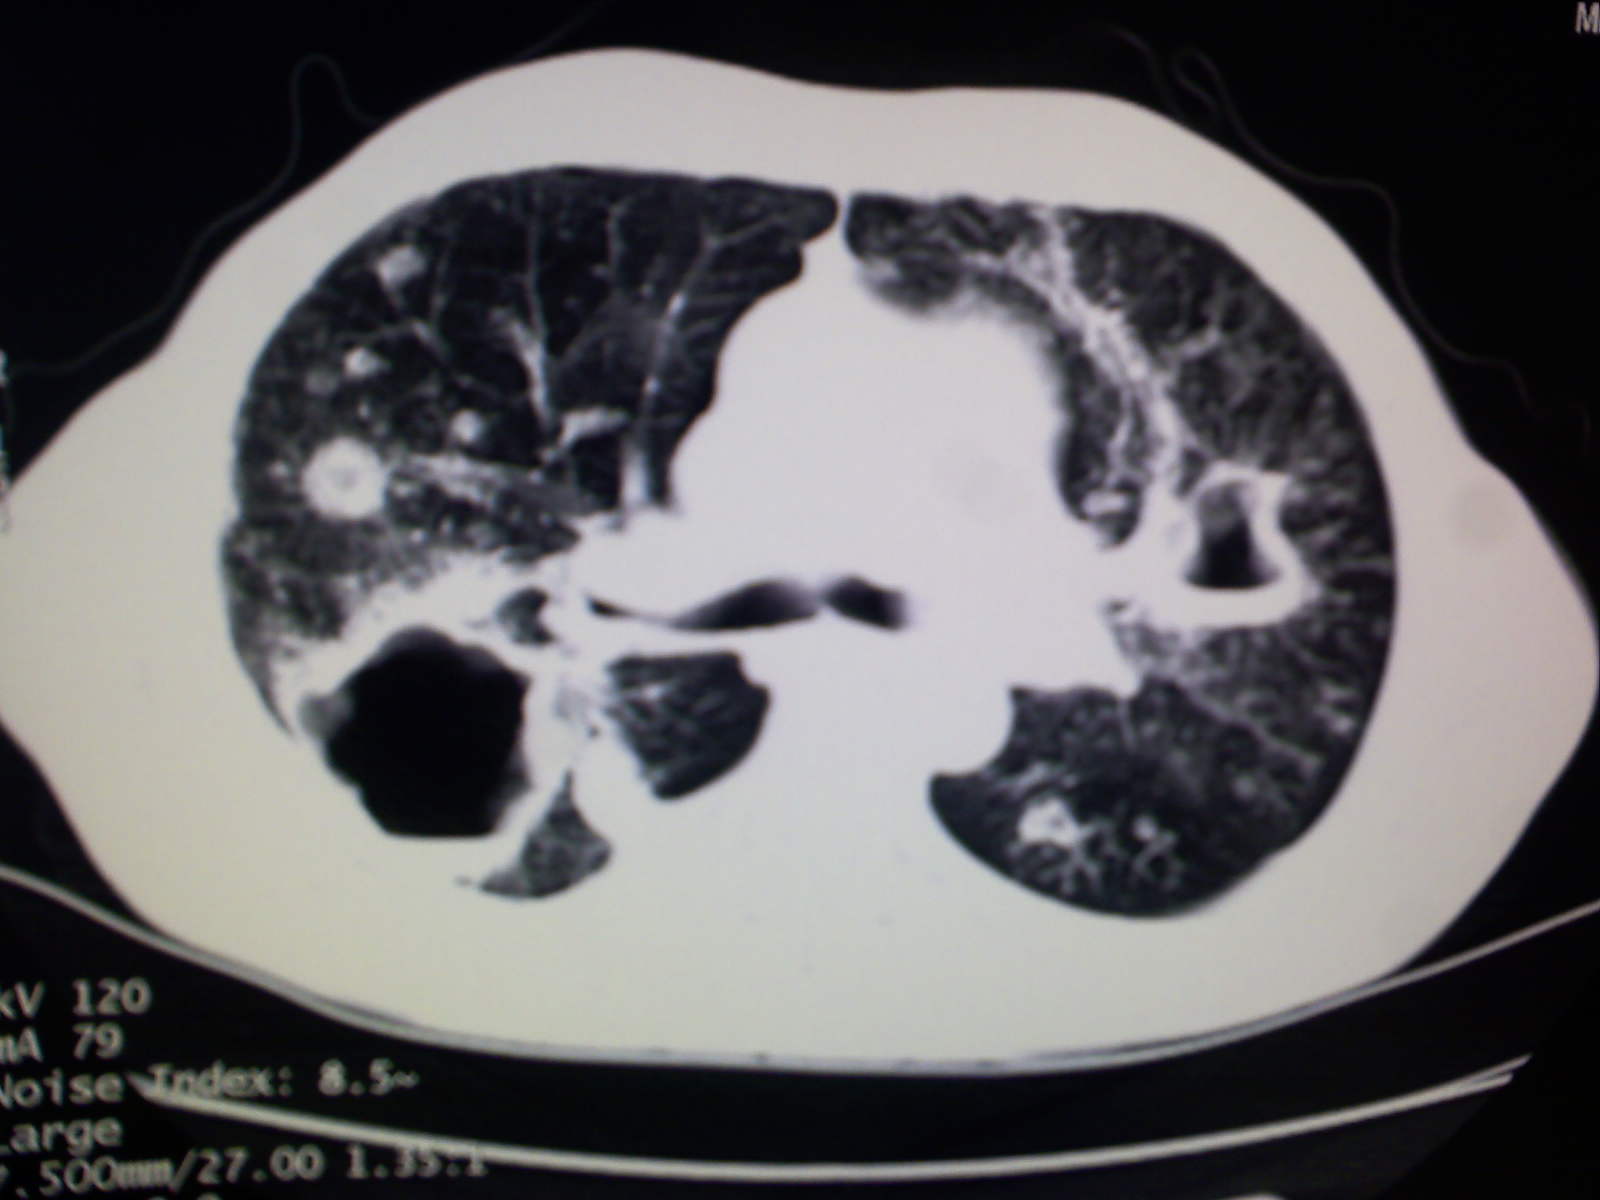

以下是引用卜一在2009-4-11 15:50:00的发言:[br]双肺继发性肺结核伴空洞形成,不排除合并霉菌感染!(病灶呈多形态 多特征 散在分布)。另:合并支气管扩张征伴感染!

以下是引用主力军在2009-4-11 15:55:00的发言:[br]两肺继发性肺结核可能性大。

以下是引用康鹏在2009-4-11 16:30:00的发言:[br]双肺继发性肺结核伴空洞形成合并感染[br]支气管扩张合并感染